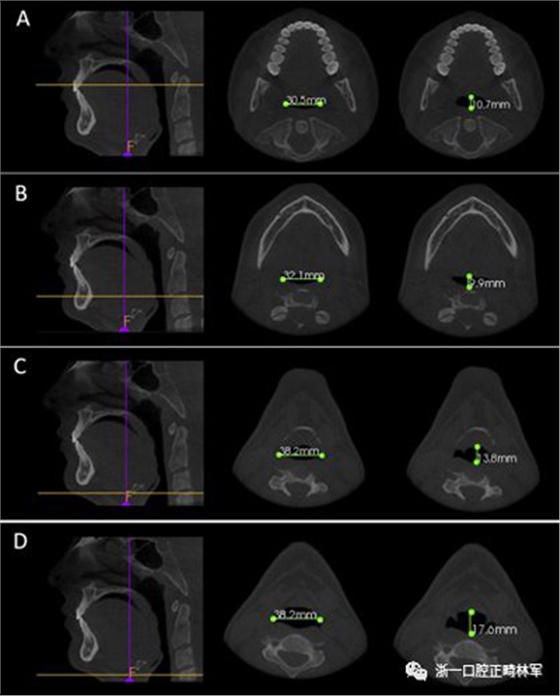

下頜骨前后角度的測量(下頜AP角),下頜橫角(TA下頜骨)和舌骨橫角(TA舌骨)。測量結(jié)果列于表I和圖1-4中。

圖2. A,LLC1和APC1; B,LLC2和APC2; C,LLC3和APC3; D,LL會厭和AP會厭。